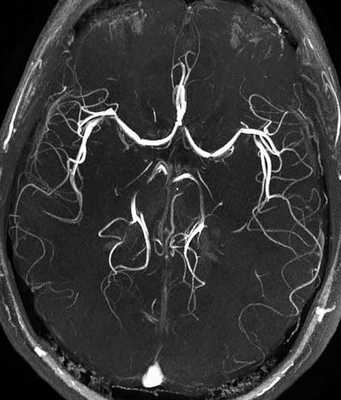

МРТ изображение артерий головного мозга

Магнитно-резонансная томография позволяет не только увидеть строение артерий, но и оценить просвет сосуда и визуализировать сосудистую стенку. Благодаря МРТ диагностика заболеваний стала возможна на самых ранних этапах их возникновения.